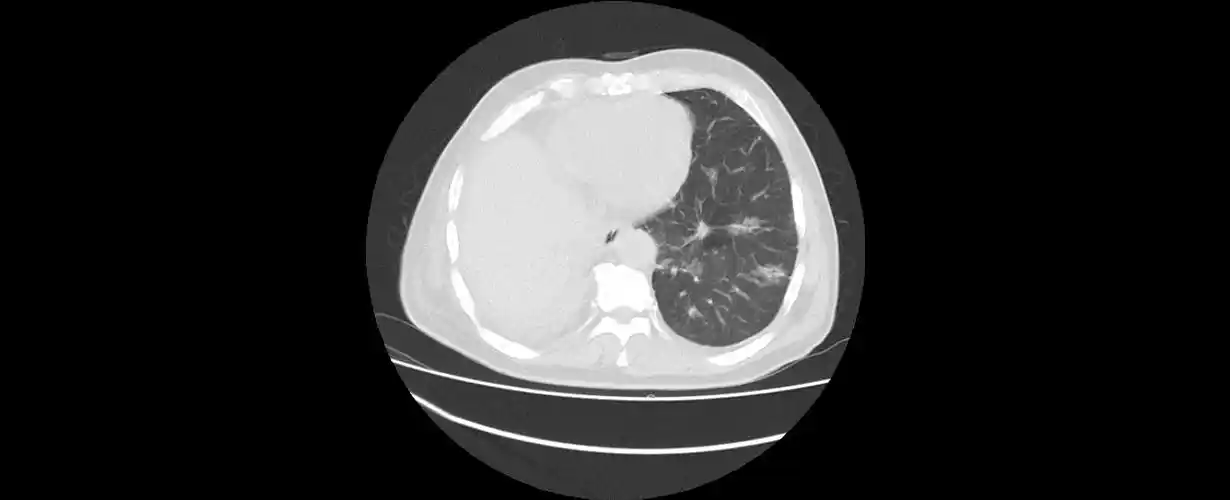

中央型肺癌ct

在ct上,肺癌按照发生部位可以分为以下3种类型: 1,中央型肺癌:指肿瘤

1例左下肺中央型鳞癌患者,斜裂不发育,肿瘤侵犯下叶支气管和上叶舌段

8cm,考虑中央型肺癌可能;纵隔多发增大淋巴结.